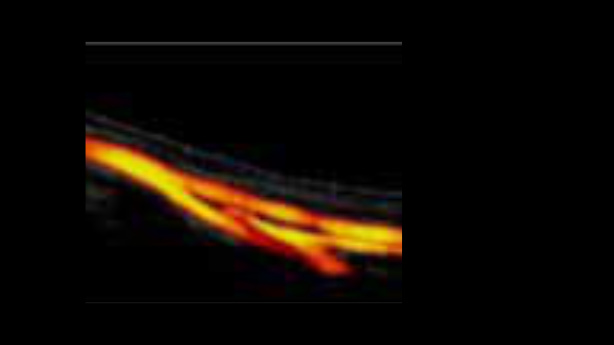

System ultrasonograficzny Zeus jest wyposa?ony w?przyjazny interfejs u?ytkownika i??atwe w?u?yciu funkcje umo?liwiaj?ce skuteczne skanowanie. Jego wszechstronne funkcje obejmuj? ultrasonografi? jamy brzusznej, naczyniow?, ma?ych narz?d├│w i?uk?adu mi??niowo-szkieletowego, zwi?kszaj?c pewno?? diagnostyczn?.